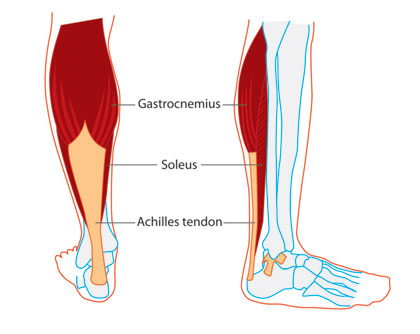

Ο μυς της γάμπας, βρίσκεται στο κάτω μέρος του ποδιού και στην πραγματικότητα αποτελείται από δύο μύες, τον γαστροκνήμιο που είναι ο μεγαλύτερος και τον υποκνημίδιο που είναι ο μικρότερος.

Ο γαστροκνήμιος (gastrocnemius) είναι ο μεγαλύτερος μυς της γάμπας που αποτελεί το ορατό εξόγκωμα κάτω από το δέρμα. Το γαστροκνήμιο έχει δύο μέρη ή «κεφάλια» που μαζί δημιουργούν ένα σχήμα διαμαντιού.

Ο υποκνημίδιος (soleus) ή πελματικός είναι ο μικρότερος επίπεδος μυς που βρίσκεται κάτω από τον γαστροκνήμιο μυ.

Οι δύο αυτοί μύες συγχωνεύονται στη βάση του μυός της γάμπας. Ο σκληρός συνδετικός ιστός στο κάτω μέρος τους συγχωνεύεται με τον αχίλλειο τένοντα. Ο αχίλλειος τένοντας μπαίνει μέσα στο οστό της φτέρνας.